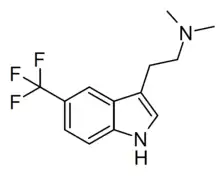

| 5-TFM-DMT | artificial | 5-CF3 | CH3 | CH3 | 5-(trifluoromethyl)-N,N-dimethyltryptamine | 2418713-32-1 |